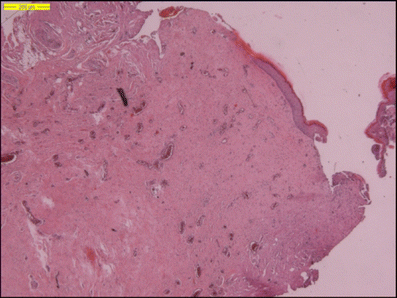

Histological examination of the resected stalk revealed connective tissue and large areas of fat. In some parts, neural tissue was noted (S100+). The absence of a lumen in the stalk was confirmed (Fig. 7).

Fig. 7

figure 7

Photomicrograph of the resected stalk in case 3. Note the large fat cells and the small parts, which are positively stained with S100. (H & E, S100 staining)